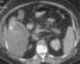

Cholecystitis with perforation

Cholecystitis is inflammation of the gallbladder. Symptoms include right upper abdominal pain, nausea, vomiting, and occasionally fever. [Source: Wikipedia ]